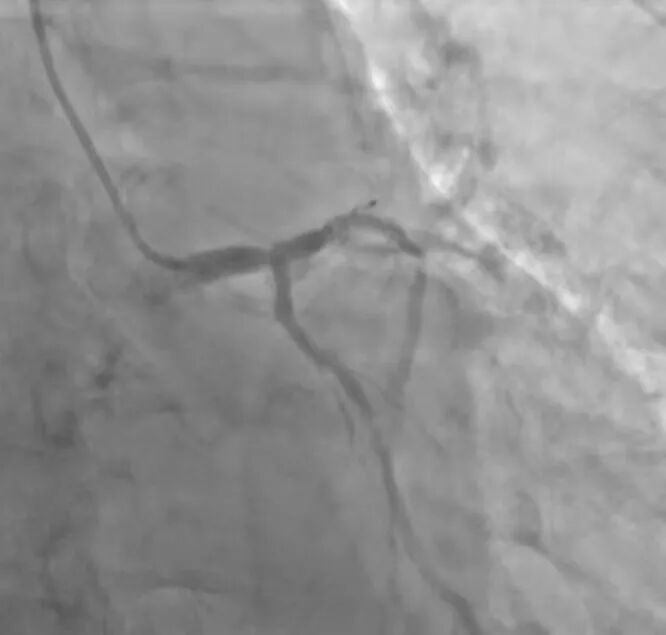

术前冠脉造影提示:.jpg

患者术前冠脉造影提示双支血管病变合并钙化